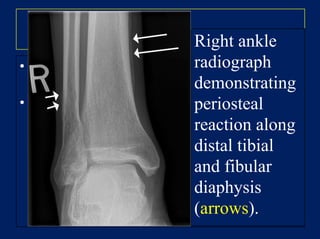

HPOA:

• Clubbing + arthralgia with joint swelling of

wrists and ankles

• X-rays show subperiosteal new bone formation

Right ankle

radiograph

demonstrating

periosteal

reaction along

distal tibial

and fibular

diaphysis

(arrows).